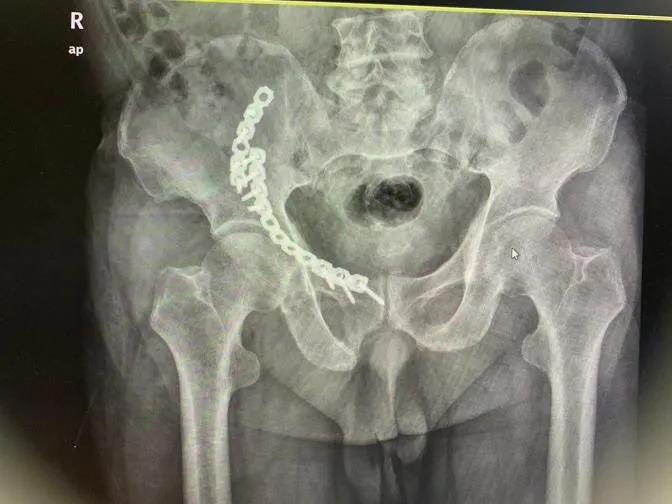

术前影像资料